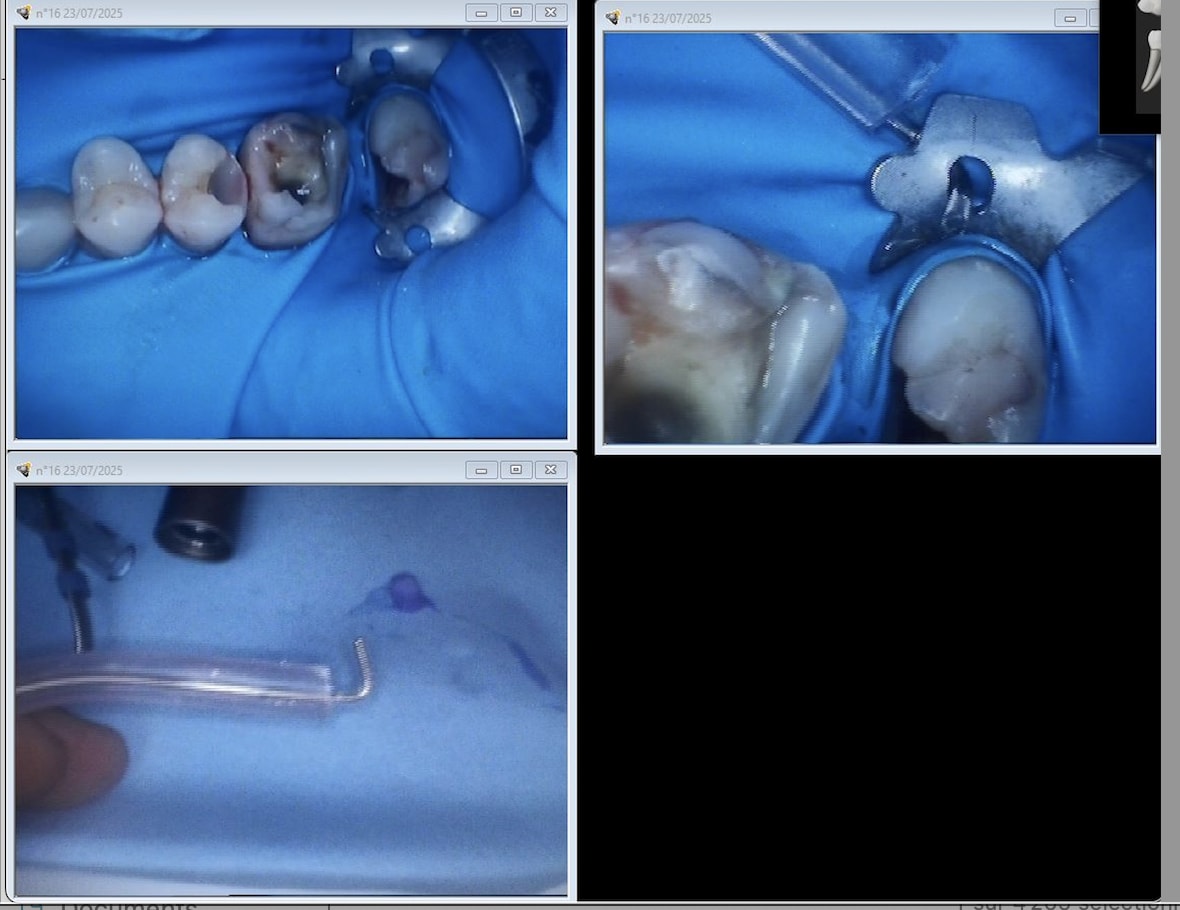

Comparaison des traitements de 2 praticiens différents au même tarif. Même patient 16 26. Pourquoi se faire chier aucun souci sur 26. ,

rien a redire sur les endos de chicot

neanmoins la question de gabzou concernant le % de cas réellement difficiles est intéressante car chicot tu illustres ce propos par des cas que tu dois trouver emblématiques datant de 2019/2020

Indépendamment du reste, il y a clairement une racine MV non traitée dont on distingue le canal, ce qui est l'anatomie standard d'une 26.

Conclusion, le praticien l'a sciemment ignorée pour aller plus vite.

On peut discuter de la rémunération, des raisons qui ont amené ce praticien à choisir de bâcler le travail, mais il est indiscutable que le praticien ne peut pas avoir ignoré avoir fait n'importe quoi.

J'ai bien précisé que tout n'est pas facile. Cette 26 l'est, je n'ai quasiment aucun doute.